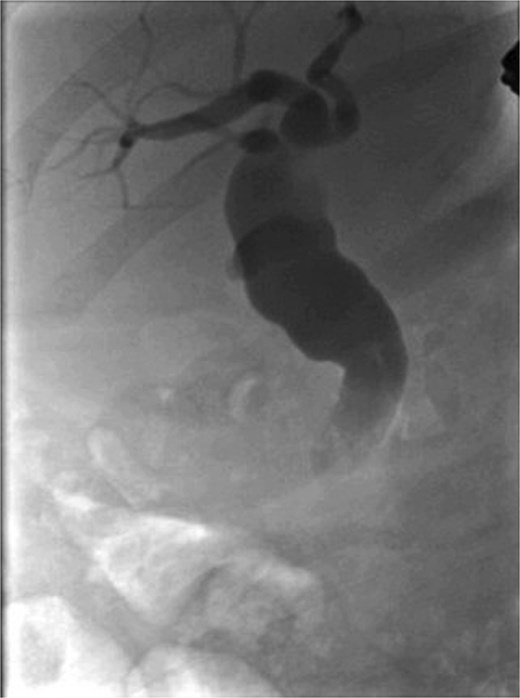

Following a brief clinical response to the initial conservative management for 24 hours, the patient started deteriorating and developed generalized peritonitis with worsening of inflammatory markers (C-reactive protein escalated to 438 mg/l). Consequently, she underwent an emergency diagnostic laparoscopy as the cause of peritonitis was not clear. Intraoperatively, it was observed that there was free bile in the peritoneal cavity, more so around the liver and the right paracolic gutter. There was also a bile collection behind the right colon and hepatic flexure of the colon, raising the possibility of a retroperitoneal source. The hepatic flexure of the colon was mobilized to assess the source of the leak. No obvious ongoing leak was noticed. As a precautionary measure, an Upper GI endoscopy was conducted intra-operatively to rule out any gastroduodenal perforation, as no obvious source of bile leak was seen from the biliary tree. This revealed the presence of bile in the stomach and confirmed normal anatomy up to the third part of the duodenum. The remaining intra-abdominal organs appeared unremarkable. Thorough peritoneal lavage was given, and 22 Fr abdominal drains were placed in the subhepatic, para-hepatic space, and pelvis, respectively, as the source of leak was not found. The following day, an endoscopic retrograde cholangiopancreatography (ERCP) was performed, which identified a small leak around the area of the cystic duct stump (Fig. 3). In response, a 5 cm-sized 7 Fr double pigtail stent was inserted into the CBD. A post-ERCP CT scan was performed to evaluate the contrast leak. The CT imaging revealed an extraluminal contrast leak originating from a defect in the posterior CBD (Fig. 4). Notably, the cystic duct stump remained intact and anterior, establishing the diagnosis of Spontaneous biliary leak from the CBD.

ERCP imaging reveals contrast leak in the cystic duct stump region.